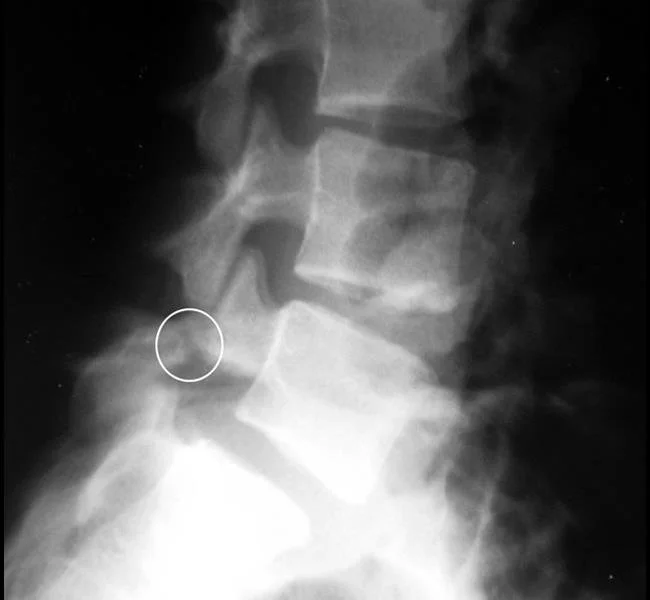

4. Lumbar Spine Stress Fracture

L5 Pars Interarticularis Stress Fracture

(Image taken from : https://orthoinfo.aaos.org/en/diseases--conditions/spondylolysis-and-spondylolisthesis/

• What is it? This involves increased stress to the vertebrae of the lower back, to a part of the spine known as the pars interarticularis. Abnormal bone stress occurs along a continuum from less stress, to more stress:

• Healthy bone

• Bone strain

• Bone stress response

• Bone stress fracture

• Common Symptoms : Lower back pain; morning pain and stiffness; pain during sport; pain at rest, pain bending backwards.

• Treatment : Imaging (x-ray and MRI). In order to allow the bone to heal, a minimum of 8-weeks off sport is recommended. This is followed by a progressive exercise programme that targets strength and control.